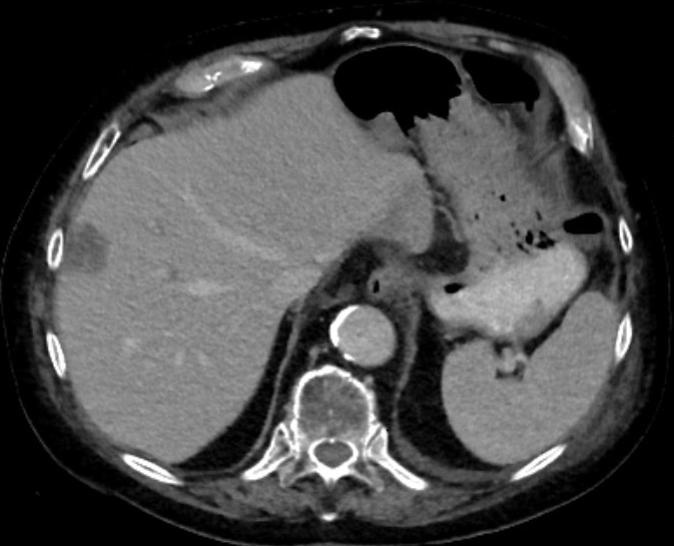

Fotos: 83jähriger Patient mit Hemikolektomie links wegen eines Adenokarzinoms der linken Kolonflexur. Nach einem Jahr Auftreten einer solitären Lebermetastase. Tumorboardbeschluss einer CT-gesteuerten Mikrowellenablation der Lebermetastase.